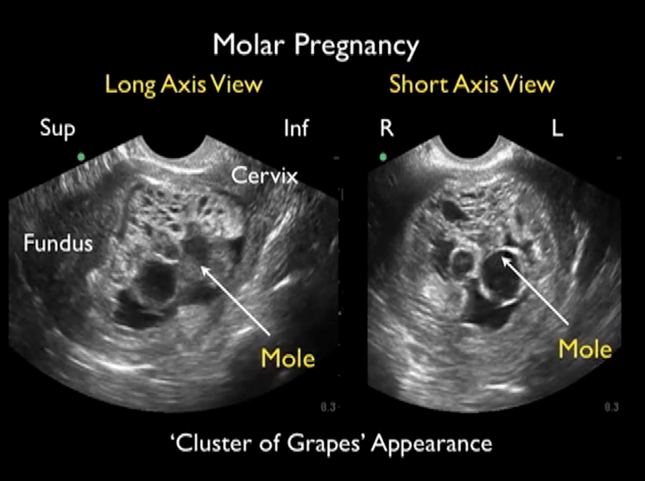

- Confirmation of pregnancy and its location, specifically to exclude ectopic pregnancy and gestational trophoblastic disease.

- Transvaginal ultrasound: Provides detailed images of the uterus, ovaries, and early pregnancy structures.

- Transabdominal ultrasound: Used for broader overviews of the abdominal cavity and later in pregnancy to assess fetal growth, placental location, and amniotic fluid volume.